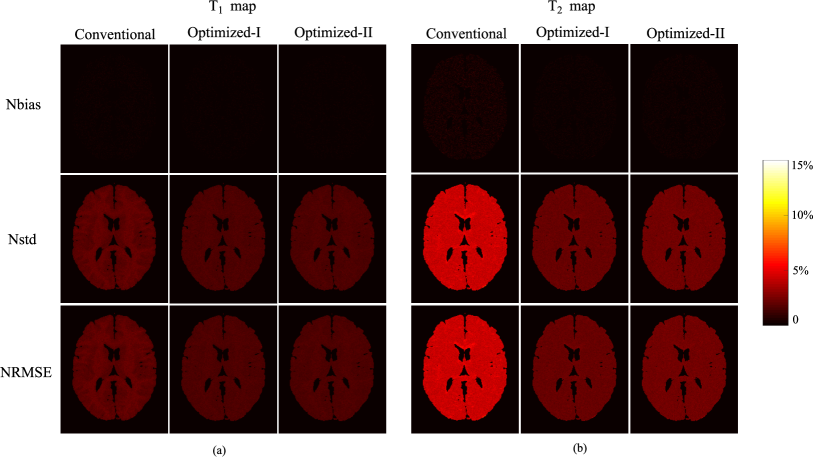

Refer to caption

Figure 9: Reconstructed parameter maps from the highly-undersampled MR fingerprinting experiments (N=400𝑁400N=400 and SNR=33dBSNR33dB\mathrm{SNR}=33~{}\mathrm{dB}), using the acquisition parameters from the conventional scheme, Optimized-I, and Optimized-II. (a) Reconstructed T1subscript𝑇1T_{1} maps and associated relative error maps. (b) Reconstructed T2subscript𝑇2T_{2} maps and associated relative error maps. Note that the overall error is labeled at the lower right corner of each error map, and the regions associated with the background, skull, scalp, and CSF were set to be zero.

Figure 10: Bias-variance analysis of the reconstructed parameter maps from the highly-undersampled MR fingerprinting experiments (N=400𝑁400N=400 and SNR=33dBSNR33dB\mathrm{SNR}=33~{}\mathrm{dB}), using the acquisition parameters from the conventional scheme, Optimized-I, and Optimized-II. (a) Normalized bias, standard deviation, and root-mean-square error for (a) T1subscript𝑇1T_{1} maps and (b) T2subscript𝑇2T_{2} maps. The regions associated with the background, skull, scalp, and CSF were set to be zero.

Fig. 10 shows the normalized bias, standard deviation, and root-mean-square error maps for the reconstructed T1subscript𝑇1T_{1} and T2subscript𝑇2T_{2} maps from the MC simulations (with 100 trials). Clearly, Optimized-II reduces the normalized standard deviation and root-mean-square error for both T1subscript𝑇1T_{1} and T2subscript𝑇2T_{2} maps, compared to the conventional scheme. Moreover, with smooth magnetization evolutions, Optimized-II reduces the bias compared to Optimized-I. This further illustrates the merit of introducing the constraint on the flip angle variations for the highly-undersampled experiments.